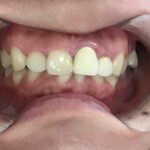

大人になってからの歯並びで叢生や八重歯、出っ歯などがありますが、

そうです。横に生えてきたり、前後に生えてきたりいわゆる叢生になってしまいますね。